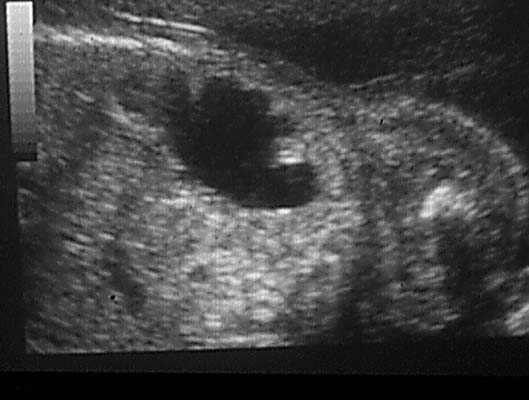

Anéchogène ovalaire